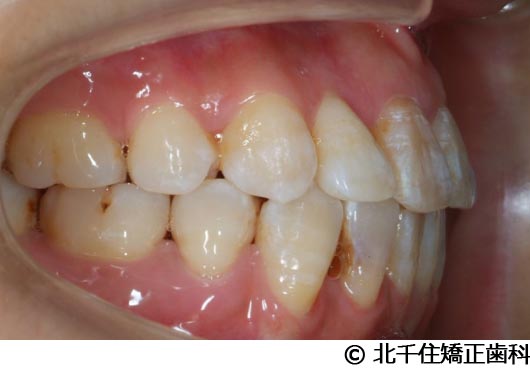

【症例4】下顎前突

- 治療前

- 治療後

- 治療名

- 下顎前突

- 費用

- 1,226,000円(税込)

- 期間

- 2年10ヵ月

- 治療回数

- 32回

- 通院頻度

- 1ヵ月ごと

- 年齢・性別

- 28歳5ヵ月・女性(初診時)

治療内容

-

患者様の症状

主訴:デコボコ、笑顔のとき歯がきれいに見えるようにしたい

治療方法

骨格性の下顎前突および開咬、上顎第二小臼歯と下顎第一小臼歯4本抜歯してワイヤー矯正(セラミックブラケット)。

治療結果

骨格性下顎前突および開咬に対し、抜歯を併用した矯正治療により歯列および咬合関係の調整を行った症例である。治療後は保定装置を使用し、歯列および咬合の安定維持を目的として定期的な経過観察を行っている。

※治療結果は個人差があります。

治療を行う上での注意点(リスク・副作用)

歯磨き不良に伴うカリエスや歯周病、歯根吸収など。